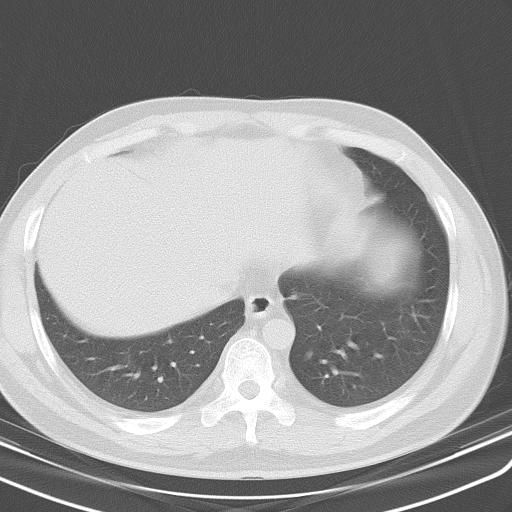

患者男性 35 主因发热咳嗽四天,血象不高,心肺听诊未见异常,无其它病史及传染病接触史。

两肺散在大小不等小结节影,下野较多,纵隔淋巴结增大。考虑:1、慢性血播性肺结核;2、霉菌病?3转移瘤待排。

该病人肺内多发结节,右肺门似有肿大淋巴结,肺结节病也要考虑

肺内纵隔多发结节,肺内以外周为著,首先考虑转移瘤

两肺多发结节,部分病灶边缘不清,且示毛玻璃影。分布特点为沿血管支气管分布。

结合临床考虑;1,炎性肉芽肿性病变;霉菌?过敏性肺炎?2,韦格氏肉芽肿。3,转移瘤。

纵隔内多发肿大淋巴结,两非弥漫性小结节状病灶,分布范围为肺外围为主,首先考虑为肺内和纵隔内转移性病变。(前不久我科室就遇到一女性38岁,肺癌伴肺内弥漫性转移)

双肺散在多发类圆形结节灶,边缘较光滑,纵隔淋巴结肿大,考虑转移瘤

淋巴结近呈对称性肿大,肺部多发结节,首先考虑结节病,其次考虑转移瘤。